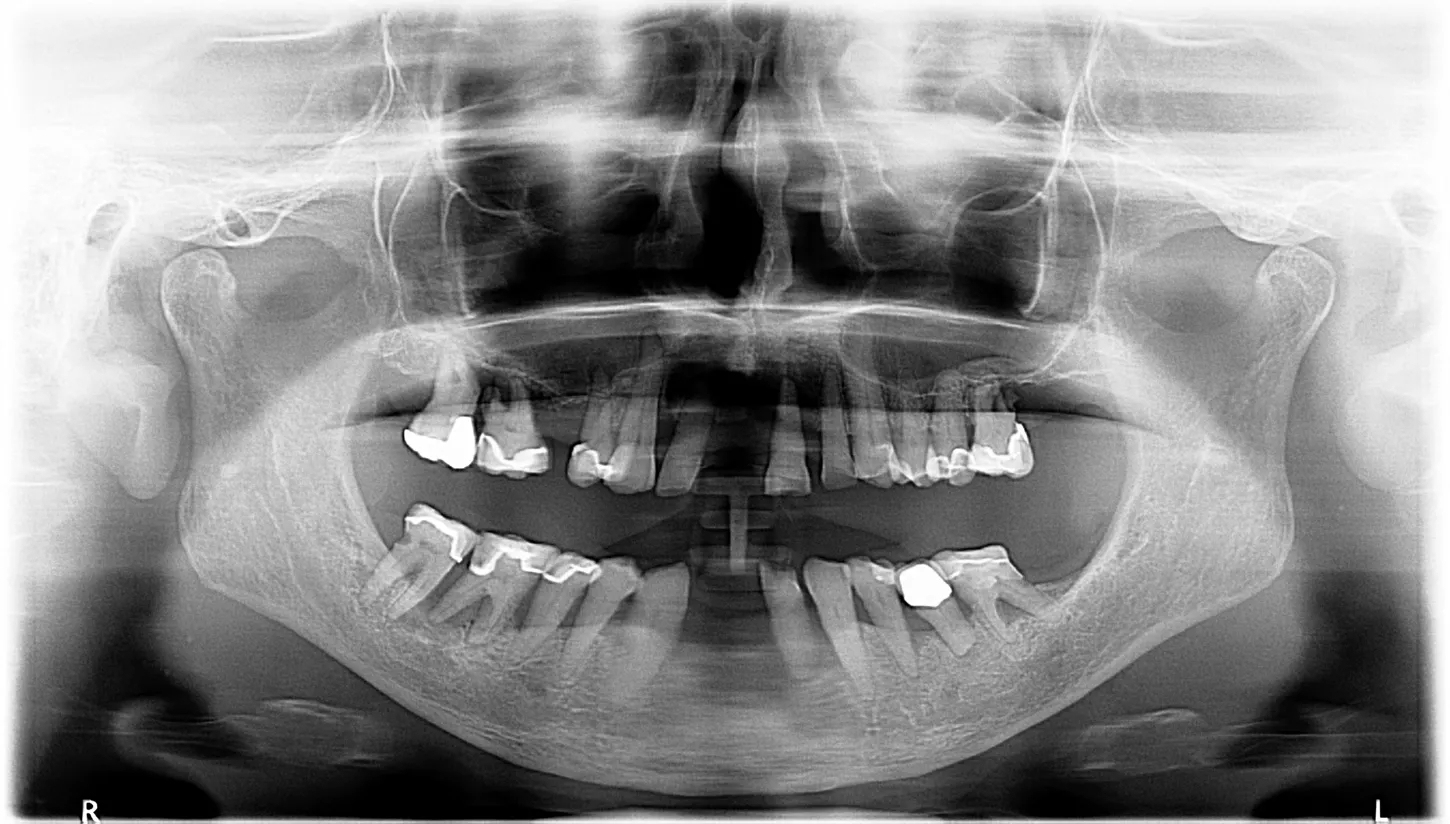

1.Pre-operation radiograph:

Clinical examination with x-ray showing a poor prospective for long-term prosthetic life of teeth on the lower jaw. In the upper jaw, teeth 13, 12, 22, 23, 24 and 25 were permanently preserved following preliminary treatment.

12.  The postoperative OPG shows the implant placement as planned

17.  Final control OPG with the complete treatment of the upper and lower jaw.